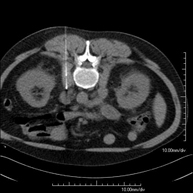

- Abdomen y pelvis- TC Abdomen Prueba diagnóstica que consiste en obtener imágenes del abdomen de alta definición anatómica (hígado, vesícula biliar, vía biliar, páncreas, bazo, estómago, intestinos, riñones, estructuras vasculares, vejiga, útero y ovarios, etc.) mediante el empleo de un equipo de TC (Tomografía Computarizada). Dichas imágenes se estudian posteriormente en una estación de trabajo que permite reconstrucciones bidimensionales en diferentes planos del espacio, y también reconstrucciones 3D (volumétricas). La mayoría de estudios requieren el empleo de contraste yodado para mejorar la definición de las imágenes. Prueba diagnóstica que consiste en obtener imágenes del abdomen de alta definición anatómica (hígado, vesícula biliar, vía biliar, páncreas, bazo, estómago, intestinos, riñones, estructuras vasculares, vejiga, útero y ovarios, etc.) mediante el empleo de un equipo de TC (Tomografía Computarizada). Dichas imágenes se estudian posteriormente en una estación de trabajo que permite reconstrucciones bidimensionales en diferentes planos del espacio, y también reconstrucciones 3D (volumétricas). La mayoría de estudios requieren el empleo de contraste yodado para mejorar la definición de las imágenes.

- TC Abdominopélvico Prueba diagnóstica que consiste en obtener imágenes bi y tridimensionales del abdomen y de la pelvis de alta definición anatómica (estructuras óseas, estructuras vasculares, hígado, páncreas, vesícula biliar, riñones, glándulas suprarrenales, bazo, intestino delgado y grueso, vejiga, útero y ovarios, próstata y vesículas seminales, uréteres, etc.) mediante el empleo de un equipo de TC (Tomografía Computarizada). La mayoría de estudios requieren el empleo de contraste yodado. Prueba diagnóstica que consiste en obtener imágenes bi y tridimensionales del abdomen y de la pelvis de alta definición anatómica (estructuras óseas, estructuras vasculares, hígado, páncreas, vesícula biliar, riñones, glándulas suprarrenales, bazo, intestino delgado y grueso, vejiga, útero y ovarios, próstata y vesículas seminales, uréteres, etc.) mediante el empleo de un equipo de TC (Tomografía Computarizada). La mayoría de estudios requieren el empleo de contraste yodado.